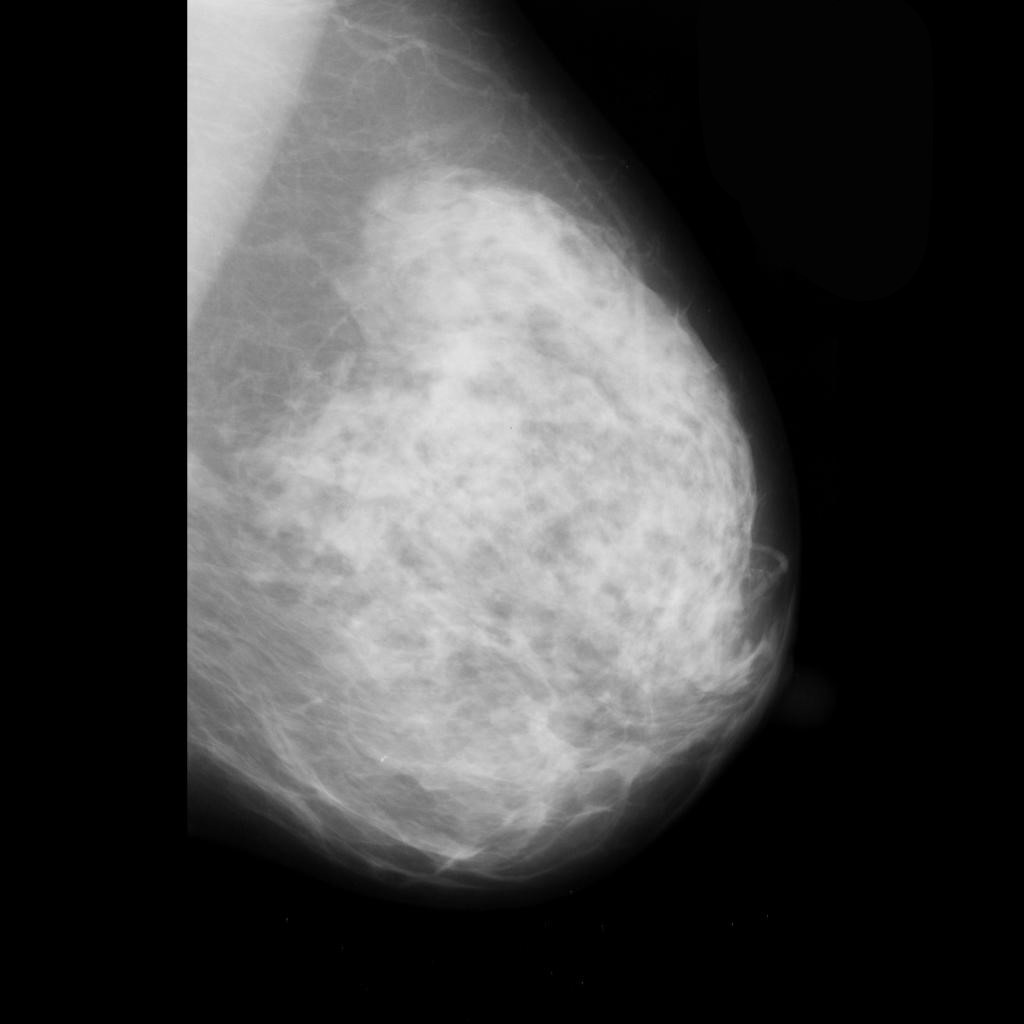

malignant